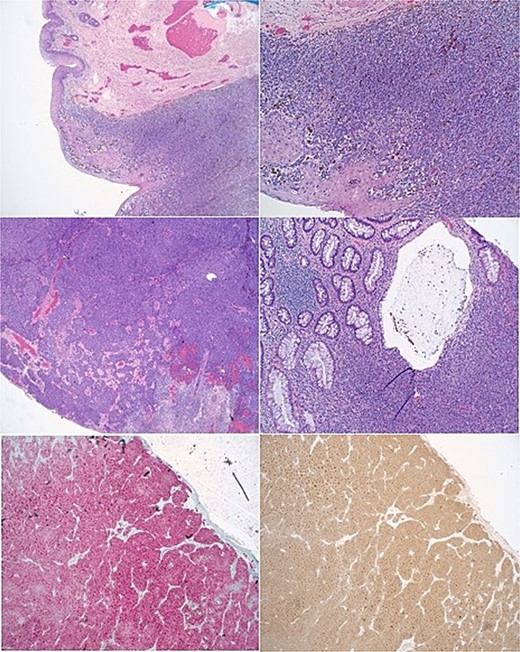

During the physical examination, a large 4-cm posterior midline bilobed friable mass was observed at the anal verge, exhibiting bleeding upon contact (Fig. 1). No preoperative laboratory investigations were conducted. Subsequently, the patient underwent rectal examination under anesthesia, revealing an ~4 cm mass at the anal verge characterized by friability and hardness with a thrombosed component. The mass was excised, and pathological analysis confirmed a diagnosis of malignant melanoma (see Fig. 2 for pathology images).

Images of anal melanoma on physical exam pre-surgical excision.